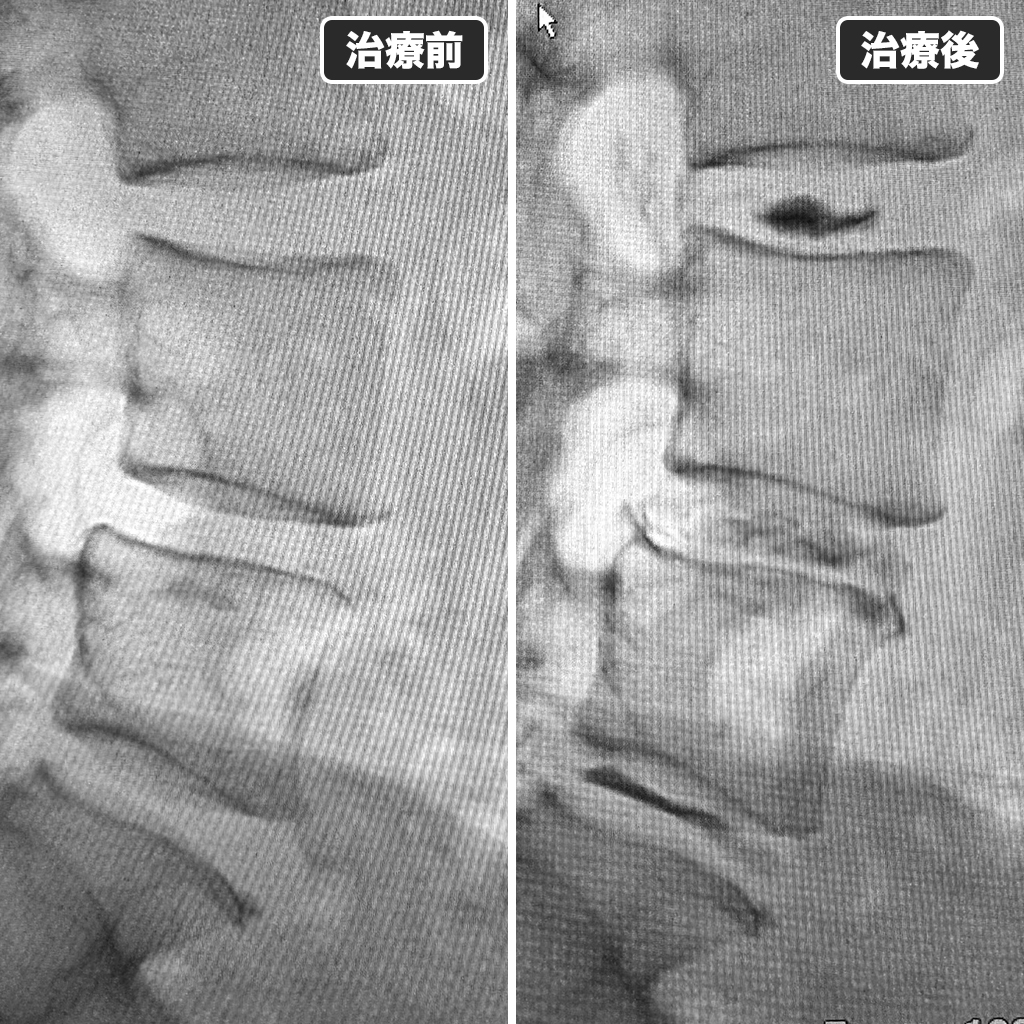

治療前後のレントゲン写真

治療前後のレントゲン写真です。左側が治療前で右側が治療後になります。神経症状が改善するには数ヵ月以上必要であるとご説明させて頂きました。